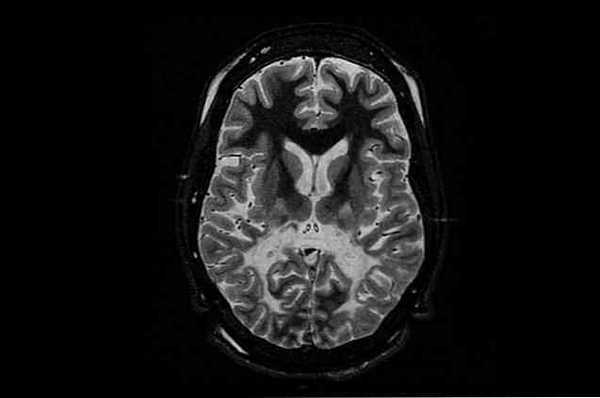

Анализ мочи и крови сразу выявляет высокую концентрацию ацетиласпарагиновой кислоты. Процесс проведения МРТ затруднителен, так как возраст пациентов очень мал, поэтому могут возникать неточности в диагностике. МРТ помогает выявить губчатую дегенерацию нервных волокон миелинового жирового слоя, а также набухание астроцитов и деформацию (удлинение) митохондрий. Концентрация аспартоацилазы в кожных фибробластах у носителей болезни Канавана приблизительно в два раза ниже нормы. Магнитно-резонансная спектроскопия показывает наивысшую концентрацию ацетиласпарагиновой кислоты в головном мозге. Особенно важен биохимический анализ крови и мочи, которые и дают заключение диагноза, играют решающую роль.

Болезнь Канавана представляет для невролога определенные сложности в диагностике, поскольку демиелинизирующий процесс наблюдается при целом ряде как врожденных, так и приобретенных заболеваний. Стандартные методы первичного неврологического обследования, такие как электроэнцефалография и ультрасонография не выявляют специфических изменений. Проведение МРТ головного мозга затруднено из-за слишком раннего возраста пациентов. Наиболее достоверным методом, позволяющим диагностировать болезнь Канавана, является анализ мочи на N-ацетил-аспарагиновую кислоту.

Обычно, если наблюдаются эти признаки, ребенку обычно проводят исследование нейровизуализации, чтобы проверить, нет ли у него признаков лейкодистрофии, таких как более низкая плотность белого вещества. Примечательно, что этот тест менее эффективен у детей с началом болезни Канавана в среднем детстве или в подростковом возрасте..